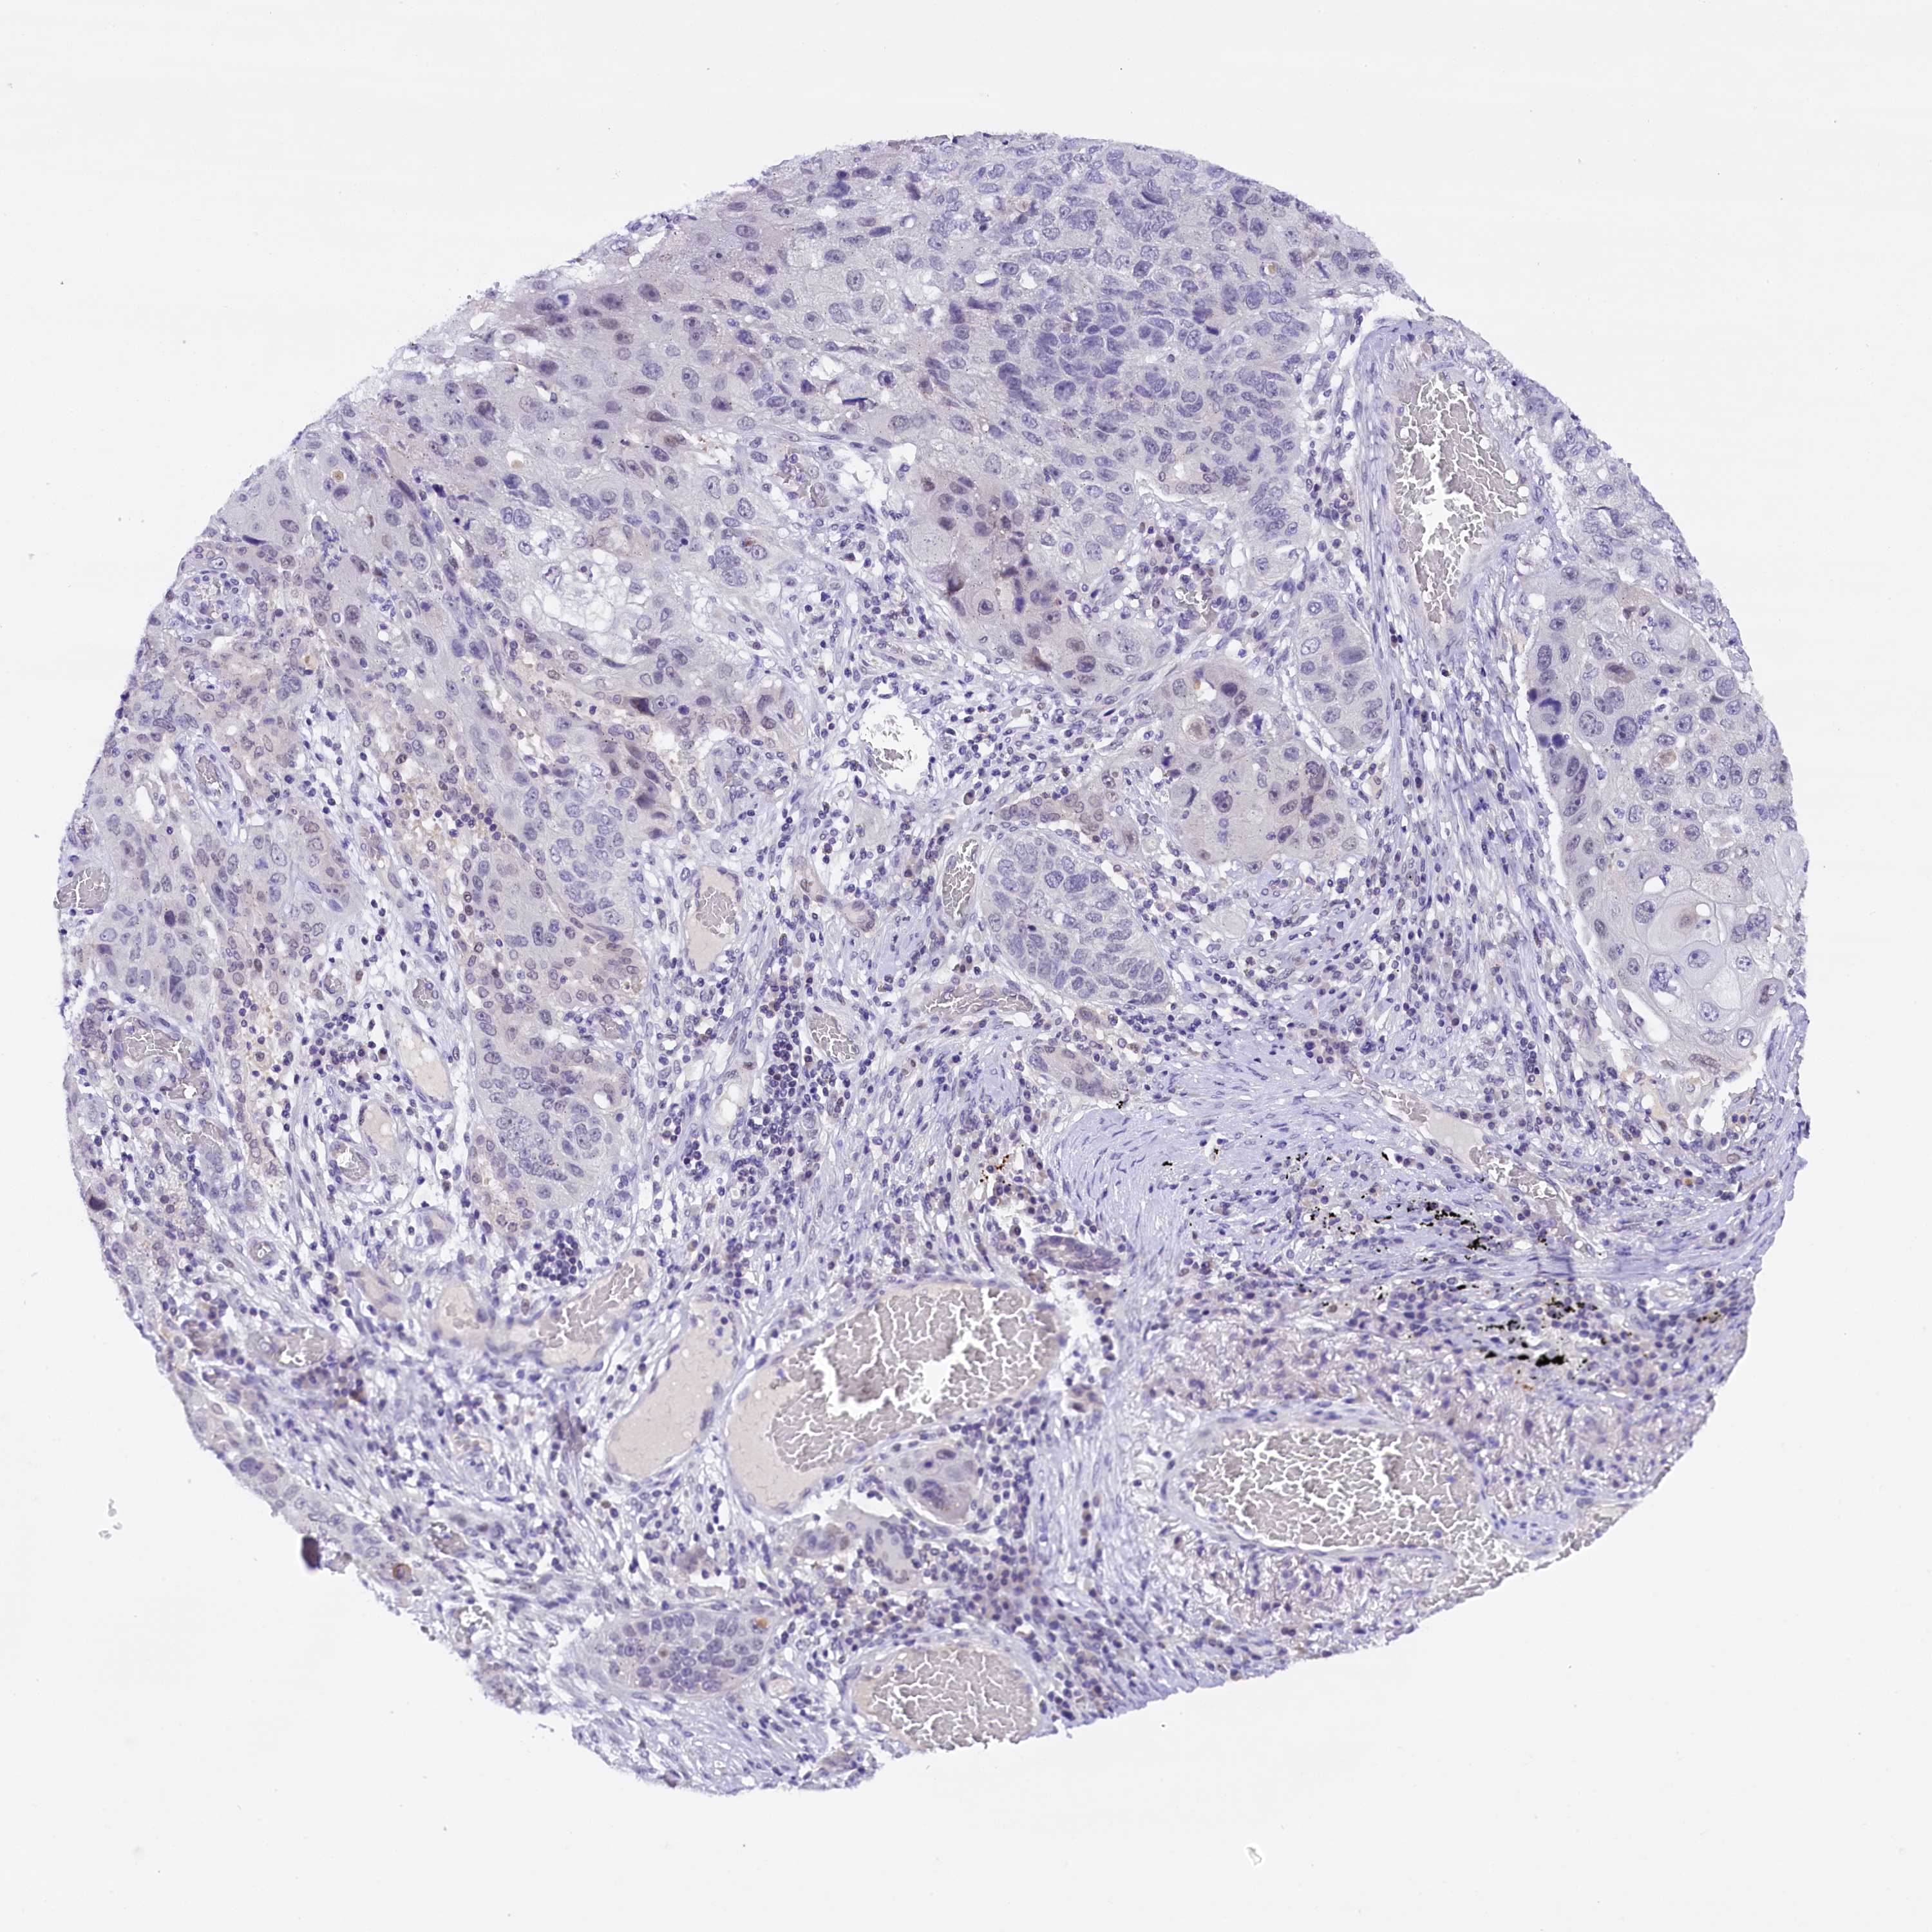

IQCN

CANCER LUNG CANCER Show tissue menu

LUAD TCGA LUAD VALIDATION LUSC TCGA LUSC VALIDATION PROTEIN LUAD CPTAC PROTEIN LUSC CPTAC PROTEIN EXPRESSION

ANTIBODIES

AND

VALIDATION